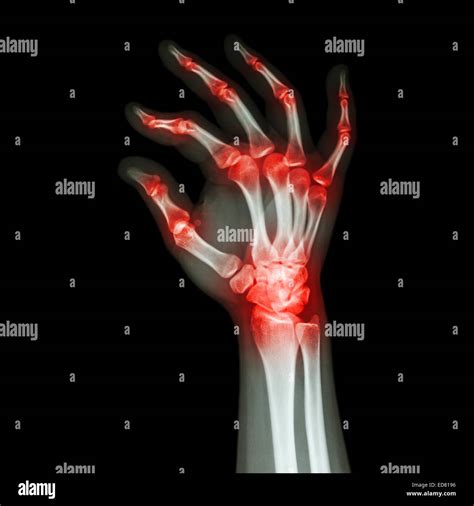

A gout attack in the hand often occurs suddenly, frequently waking the patient up in the middle of the night. Because the skin over the joints of the fingers and wrists is relatively thin, the symptoms can appear very dramatic. Common signs include:

• Intense Joint Pain: The pain is often described as burning, throbbing, or crushing, making even the lightest touch—such as the brush of a bedsheet—excruciating.

• Swelling and Inflammation: The affected joint will become visibly swollen, and the surrounding area may become warm to the touch.

• Redness or Discoloration: The skin over the joint often turns deep red or even purplish.

• Limited Range of Motion: As the flare-up progresses, the joint may become stiff, preventing you from bending or straightening your fingers.